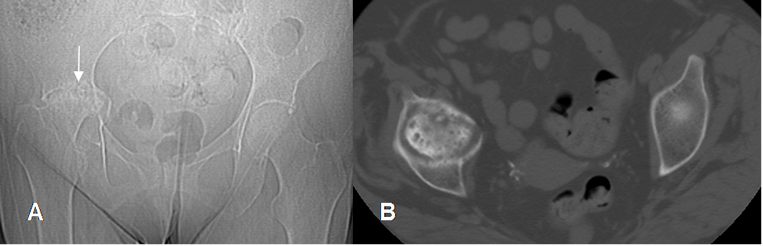

Fig 142 B. Artritis séptica.

A: Rx AP. Pérdida del espacio articular en la cadera izquierda, sin presencia de osteofitos.

B: TAC axial. Adicionalmente se encuentra alteración en la densidad de la cabeza femoral, por osteomielitis asociada.

Fig 143 B. Artritis séptica.

A: RM coronal en T1, B: RM coronal en STIR y C: RM axial en STIR. Igual paciente de la figura 142 B. Aumento del líquido articular, por artritis infecciosa. (Flechas delgadas). Se encuentra edema de la cabeza femoral, hipointenso en T1 e hiperintenso en STIR y erosión de la cortical media, por osteomielitis asociada. (Flecha gruesa). Existe colección asociada en la parte anterior de la cadera. (Punta de flecha).